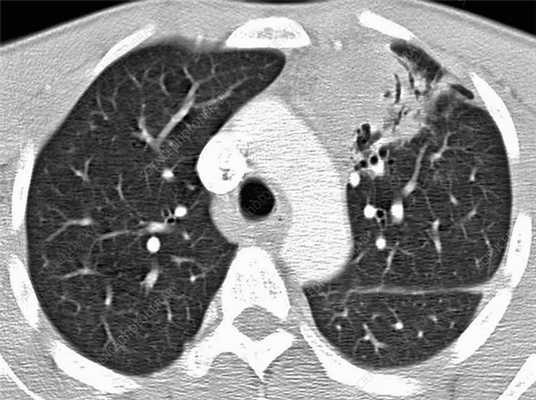

Лимфому средостения не всегда можно обнаружить на рентгенографии. При подозрении на опухоль пациентам назначают компьютерную томографию: среди онкологов она признается как наиболее эффективный и точный диагностический метод.

На КТ можно обследовать с одновременным измерением формы и объема увеличенных лимфатических узлов. Методика показывает скопление воспалительного экссудата, конгломерат опухоли, количество и расположение пораженных групп лимфоузлов.

Лимфома легких на КТ

Признаки лимфомы легких особенно выражены на четвертой стадии заболевания, когда болезнь поражает дыхательный орган. На КТ при этом будут видны увеличенные лимфоузлы, формирующие цепочки, конгломераты. При этом у пациента может также наблюдаться отек легких. Однако высокая разрешающая способность КТ позволяет выявить лимфому на ранней, первой стадии.

На КТ лимфомы, как и любые уплотнения, визуализируются сравнительно более светлым цветом. В норме воздушная легочная паренхима практически однородного темного цвета. Иногда таких уплотнений несколько и они диссеминированны. Контуры лимфомы четкие и ровные. Вокруг патологических очагов обнаруживаются участки «матового стекла».